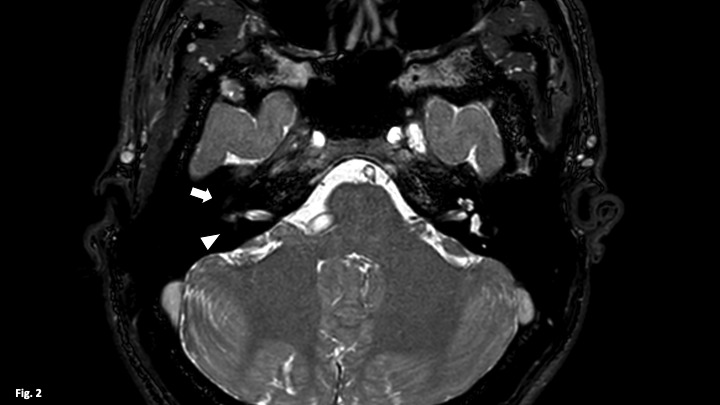

Labyrinthitis ossificans is a pathology consisting of calcification of the membranous labyrinth resulting in profound sensory deafness. It is usually due to an acute inflammatory process that progresses to ossification of the labyrinth. The clinical manifestations are irreversible hearing loss, dizziness and vomiting. It is diagnosed by computed tomography (CT) and magnetic resonance imaging (MRI). It is important to make the correct diagnosis before cochlear implantation, as ossification of the labyrinth can hinder or prevent the implantation of electrodes.